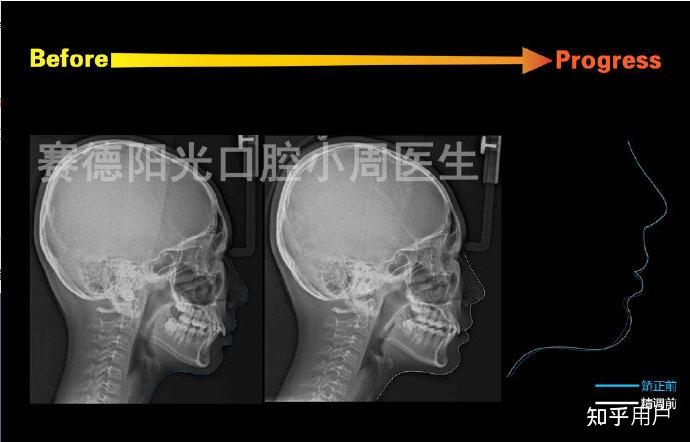

(大家可以通过这张图看看自己是骨性前突还是龅牙)

大家可以看到矫正前患者因为骨突问题,侧面嘴巴凸得特别明显,嘴唇撅起来,给人一种刻意嘟嘴的感觉。经过临床检查,再结合患者意愿,小周医生采用隐适美矫治器,通过拔牙矫正结合种植钉支抗的方案来进行回收,最终的矫正效果也很好地说明了如果牙周健康,骨量宽度足够,嘴唇其实是可以回收很多的。

这里分享一例单纯正畸改善骨性下颌后缩+嘴突的案例。患者在面诊的时候,我们通过临床检查以及头影测量,发现患者下颌后缩、嘴突的原因几乎是纯骨性的。小周医生如实告知患者,最好的方案是手术方案,这样对下颌后缩改善会很大。但患者坚持不想手术,反复在问只戴牙套能达到什么效果,其实单纯正畸能做到手术效果的60%,甚至可能还更低。经过深思熟虑,患者还是选择了相信小周医生,选择了单纯正畸的方案。并且提出两个诉求:嘴突改善一些就可以了,改善露龈笑。确定了方案后,我们一同朝着矫正目标努力,经过一年多的矫正,可以看到嘴突改善了一些,露龈笑的改善也是非常显著的。纯骨性的问题,如果患者不想手术,我们在治疗前做到充分的沟通,最终的结果还是能够达到患者满意的,毕竟不是所有人都能接受手术方案。

最后小周医生再来分享一个这样的案例,通过拔牙矫正大量回收前牙改善骨性前突的侧貌。

患者主诉明确——改善嘴突。在很多地方咨询过,得到的答复是:骨性前突,牙齿整齐,矫正改善不大,要想解决嘴突的问题只能通过手术。经检查发现,患者牙齿非常非常整齐,骨性嘴突。家人不是特别赞成她进行矫正,更别提做手术了。经过测量分析,小周医生觉得可以采用拔牙矫正的方案去代偿骨性的问题,利用种植钉支抗大量回收前牙,从而改善侧貌。不到2年的时间,患者侧颜得到了非常大的提升。对于骨性前突,从最近小周医生分享的侧貌变化案例看,无论是隐形矫正还是传统矫正也好,最关键的是种植钉的使用和患者良好的配合。